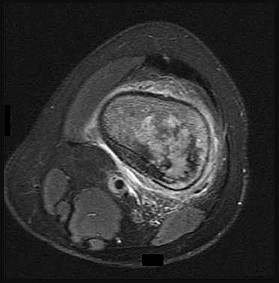

Figures 6a through 6d are the radiographs and T1-weighted sagittal and fat-saturated axial MR images of an otherwise healthy 56-year-old man who has anterior knee pain and intermittent swelling after sustaining a noncontact twisting injury. Low-power and high-power hematoxylin and eosin stained histologic specimens are shown in Figures 6e and 6f. Based on the history, radiographs, CT scan, MR imaging, and histologic findings, what is the most likely diagnosis?

The lesion in the posterior intercondylar knee notch is a benign synovial hemangioma. Intralesional calcifications, classically associated with hemangiomas, are frequently not identified on plain radiographs. The MR imaging reveals a hypervascular lesion with multiple filling defects, with hyperintensity on T2-weighted images and low-to-intermediate signal intensity on T1-weighted images. Histologically, vascular lakes within fine capillaries with a synovium on the surface of the lesion are characteristic of this condition. Many patients with synovial hemangioma have pain, swelling, stiffness, or mechanical symptoms. The correlation of symptoms with the hemangioma for this patient is unclear because there was recent trauma and a concurrent meniscus tear. Simultaneous treatment of both potential sources of pain is typically recommended. As with PVNS, the disease can be localized or diffuse. Surgical excision, either open or arthroscopic, is the recommended treatment. PVNS is the most common intra-articular tumor, but hypointensity in either the diffuse or localized type is characteristic in both T1- and T2-weighted images. Synovial sarcoma, although often found close to a joint, is not characteristically found within a joint.